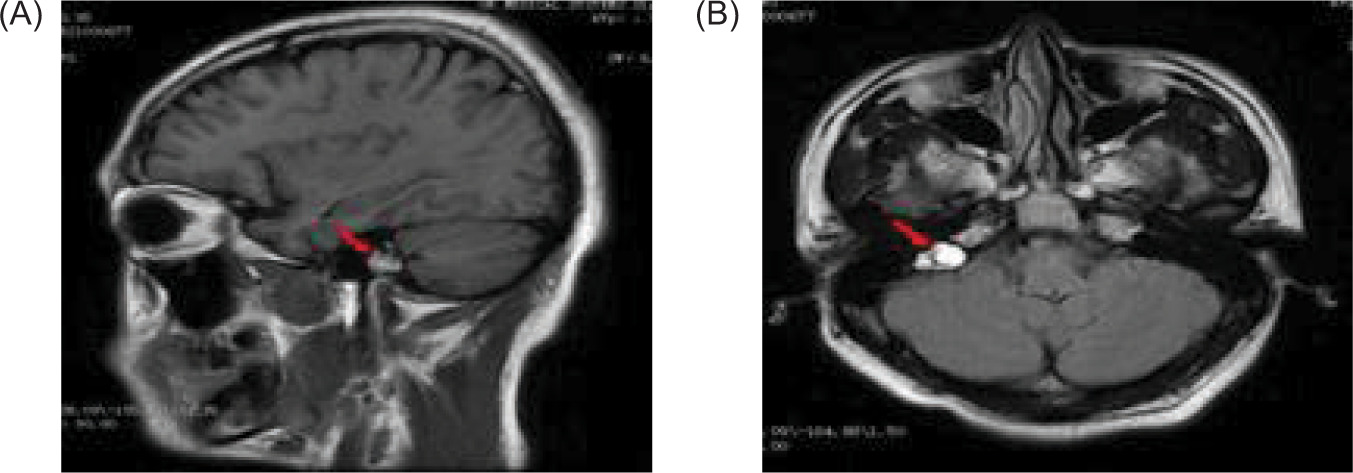

An abdominal CT on January 16, 2021 revealed renal and pancreatic masses, and an enhanced abdominal CT scan on January 18, 2021 showed multiple pancreatic cysts/cystadenomas and multiple kidney cancers in both kidneys and a small cyst in the left kidney (Figure 2). A cranial magnetic resonance imaging (MRI) done on January 29, 2021 revealed a possible mass in the right temporal bone jugular foramen, with a cross-sectional area of approximately 12×18 mm (Figure 3). The patient refused further examination of the brain and abdomen for personal reasons and denied any family history of VHL syndrome. He was diagnosed with DM and treated with tablet voglibose, 0.2 mg, three times daily (tds), and injection glargine insulin, 12 units once daily (OD). Despite the treatment, he continued to suffer from progressive weight loss over the next 6 months, losing an additional 7 kg.

Figure 3: A magnetic resonance imaging (MRI) of the cranial reveals a possible mass in the right temporal bone jugular foramen, with a cross-sectional area of approximately 12×18 mm (red arrow); (A) sagittal position, and (B) flair view.

Brain MRI revealed a cystic mass in the right cerebellar hemisphere measuring approximately 40 mm (Figure 6). Thyroid color Doppler ultrasound revealed solid and cystic nodules in both thyroid lobes (C-TIRADS: Category 3) (Figure 7). His fasting blood glucose level was 20.6 mmol/L. On November 29, 2024, he was treated with intensive insulin therapy, and his antidiabetic regimen was adjusted to injection aspart insulin, 4 units tds daily before meals and injection degludec insulin, 5 units once daily at night. The patient’s fasting blood glucose stabilized at 4.5–5.0 mmol/L, and postprandial blood glucose stabilized at 6.0–8.0 mmol/L in 3 days before discharge, and his clinical manifestations, such as polydipsia and weakness in the lower limbs, decreased significantly.

Figure 6: Magnetic resonance imaging (MRI) of the brain reveals a cystic mass in the right cerebellar hemisphere, approximately 40 mm in size (red arrow); (A) sagittal position, and (B) flair view.